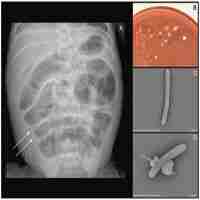

| Abstract | Long-chain 3-hydroxyacyl-CoA dehydrogenase deficiency (LCHADD) is an autosomal recessive condition of impaired beta-oxidation. Traditionally, treatment included restriction of dietary long-chain fatty acids via a low-fat diet and supplementation of medium chain triglycerides. In 2020, triheptanoin received FDA approval as an alternative source of medium chain fatty acids for individuals with long-chain fatty acid oxidation disorders (LC-FAOD). We present a case of a moderately preterm neonate born at 33 2/7 weeks gestational age with LCHADD who received triheptanoin and developed necrotizing enterocolitis (NEC). Prematurity is known as a major risk factor for NEC, with risk increasing with decreasing gestational age. To our knowledge, NEC has not previously been reported in patients with LCHADD or with triheptanoin use. While metabolic formula is part of the standard of care for LC-FAOD in early life, preterm neonates may benefit from more aggressive attempts to use skimmed human milk to minimize exposure to formula during the risk period for NEC during feed advancement. This risk period may be longer in neonates with LC-FAOD compared to otherwise healthy premature neonates. |